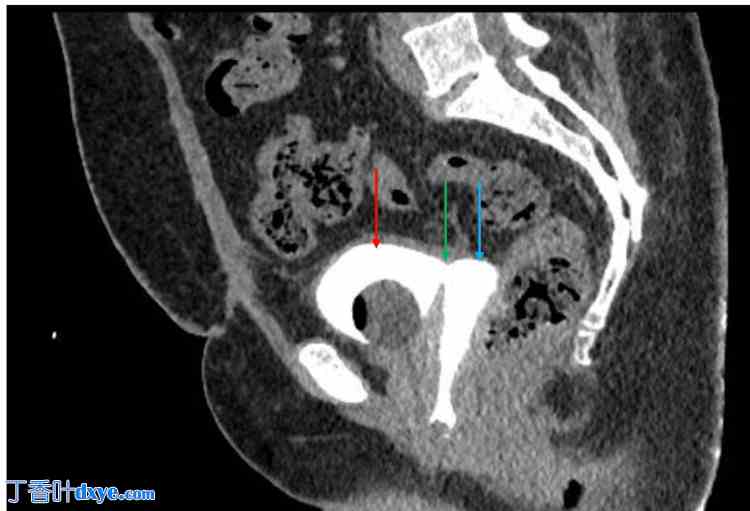

出院时,患者情况良好,生命体征稳定,无任何不适。医生建议她继续口服呋喃妥因24天,口服索利那新30天,以及对乙酰氨基酚14天。之后定期随访。出院一周后,中段尿液检查结果为阴性。术后三周,复查CT膀胱造影,未见造影剂渗漏至阴道(如图2箭头所示)。三周内,患者开始出现外阴刺激症状,使用聚维酮碘(碘伏)阴道栓剂后缓解;同时出现潮热、盗汗、盆腔疼痛和排尿困难等症状,采用激素替代疗法进行治疗。安排了门诊随访。随访期间,患者无任何不适。

图2. 术后增强CT膀胱造影。

红色箭头指向膀胱。